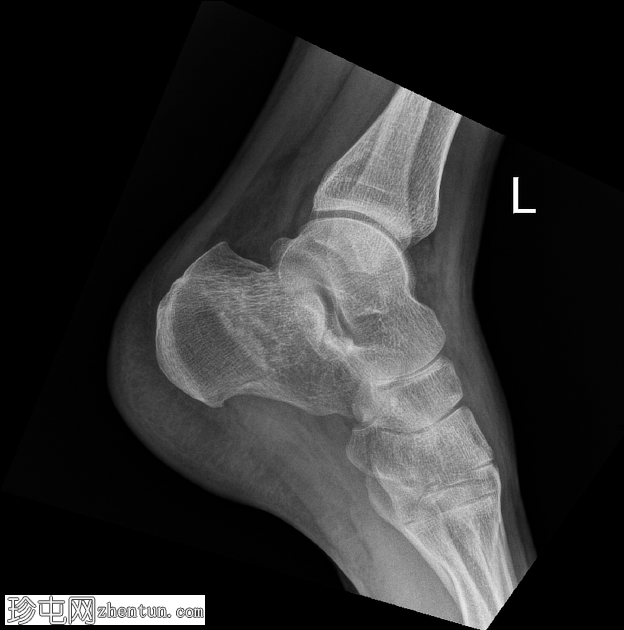

侧位片

左侧跟骨关节内粉碎性骨折。骨折线贯穿跟骨体,累及并破坏距下关节后关节面,并沿跟骨外侧可见一处骨折。骨折始于距下关节中央,向下向后延伸。跟骨整体高度降低,后关节面凹陷,Böhler角变平,Böhler角明显减小,提示后关节面凹陷。

距骨、舟骨以及外踝和后踝均完整,踝穴和韧带联合完整。距下关节和跟骰关节未见脱位。软组织肿胀亦可见。

跟骨骨折是跗骨中最常见的损伤,通常由轴向负荷力引起,例如高处坠落或高强度冲击创伤。本例左侧跟骨的侧位片和轴向片显示,关节内粉碎性骨折延伸至距下关节后关节面,伴有高度降低和后关节面凹陷。

Böhler角(由跟骨前后关节面连线的交点定义)显著减小(约5-10°,正常值为20-40°)。Böhler角的减小反映了后关节面的塌陷,并提示跟骨结构性损伤严重。